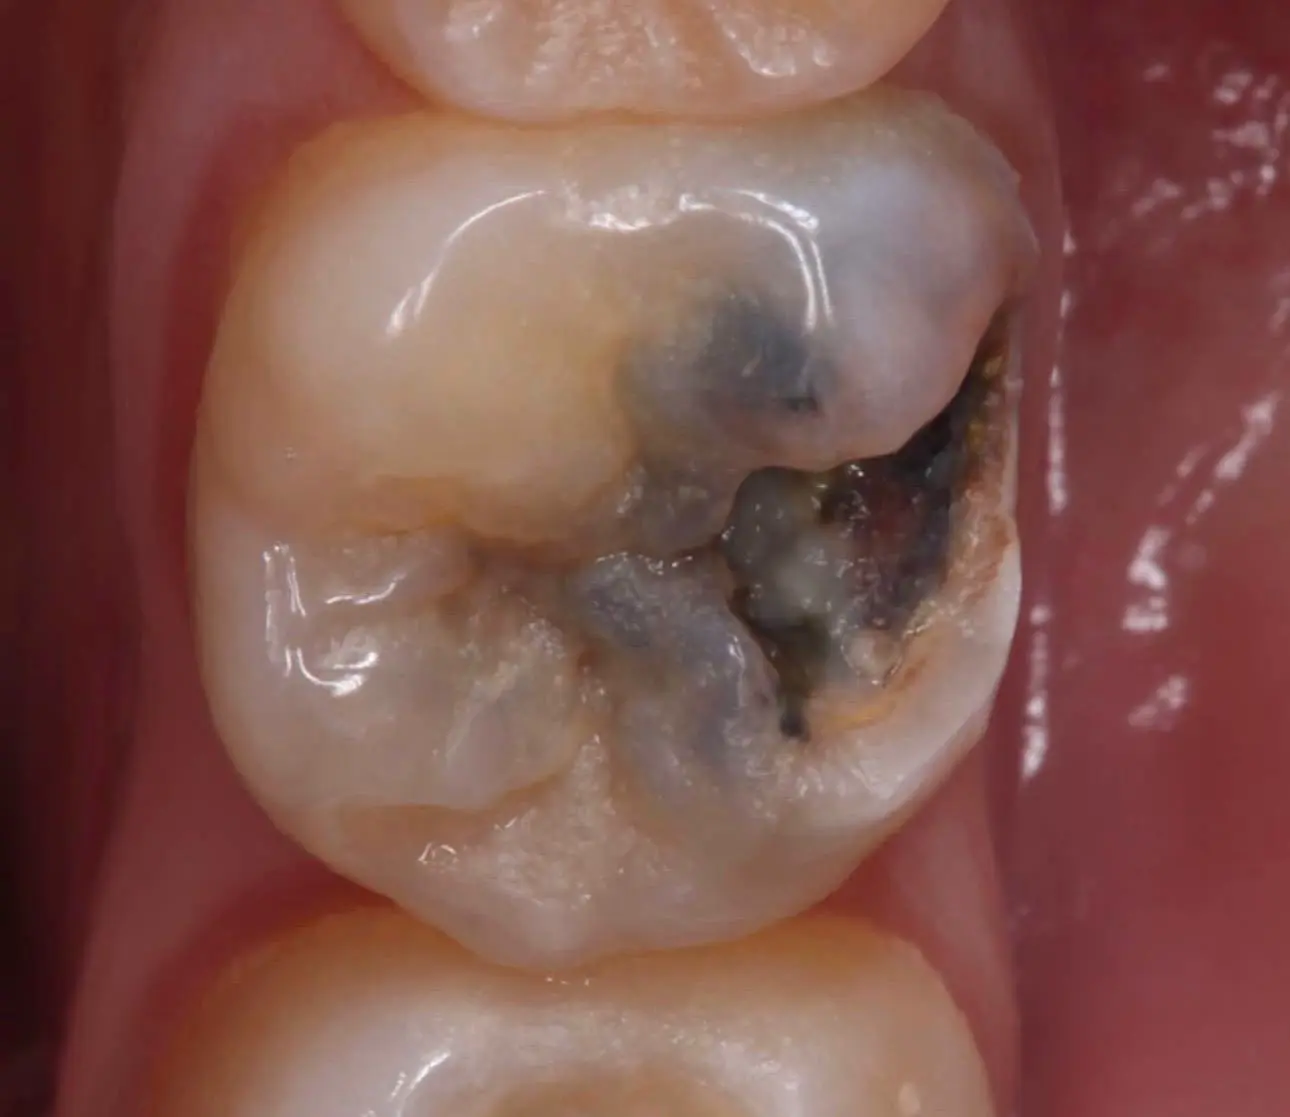

قبل

بعد